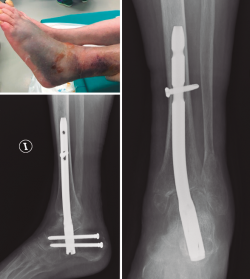

Clavo tibiotalocalcáneo

Buscando los objetivos deseables en el anciano frágil de aportar una estabilidad primaria suficiente que permita la carga temprana, en una sola cirugía y con la menor agresión posible, varios estudios han publicado sus experiencias tratando este tipo de fractura en casos seleccionados mediante el uso de enclavado retrógrado TTC(12,61,62,63,64,65) (Figura 6).

Lemon(61) en 2005 publica el primer artículo utilizando clavos, en lugar de Steinmann transarticulares, para la estabilización indirecta de fracturas inestables de tobillo en el anciano. En su serie de 12 pacientes, con edad promedio de 84 años, todos los pacientes iniciaron la carga completa el primer día postoperatorio, no presentando complicaciones óseas ni de partes blandas y consiguiendo en la mayoría de los casos la situación funcional previa.

En 2014, Al-Nammari(62) publica una serie de 48 pacientes frágiles, de edad promedio de 82 años, tratados mediante enclavado TTC usando un clavo largo de fémur, ya que este autor recomienda pasar el istmo de la tibia con el implante para evitar posibles fracturas periimplante con clavos cortos. La mortalidad a los 6 meses fue del 35%, pero el 90% de los pacientes restantes recuperaron la situación funcional previa. Entre las complicaciones, presentaron un 6% de infecciones, un 6% de rotura o aflojamiento de tornillos distales, un 4% de consolidación en mala posición no sintomática y un caso de amputación infrageniana en un paciente con fractura abierta IIIC. No presentaron ningún caso de pseudoartrosis, rotura del clavo ni fractura periimplante. En este estudio retrospectivo, el autor, aunque refiere que la decisión para este tratamiento fue esencialmente subjetiva, sin criterios de inclusión establecidos, sí define factores que pueden influir para la elección de este tratamiento: 1) pacientes con deambulación limitada a domicilio o menor de 200 metros precisando ayudas; 2) pacientes física o mentalmente demasiado frágiles como para tolerar la restricción de carga; 3) mala calidad ósea y/o de partes blandas; 4) puntuación de la American Society of Anaesthesiologists (ASA) de 3 o más; y 5) comorbilidades significativas(62). Otros factores descritos en otros artículos(12,63) que podríamos incluir para la toma de decisión serían: 6) presencia de diabetes y/o neuropatía y/o vasculopatía periférica; 7) fracturas abiertas; y 8) angulación del eje de más de 15° en al menos una proyección.

Otros estudios más recientes, tanto con clavos cortos(63,64) como largos(65) TTC, para el tratamiento de fracturas inestables de tobillo en pacientes frágiles con baja demanda funcional, presentan buenos resultados funcionales, con carga completa temprana y con bajas tasas de complicaciones, sin presentar fracturas periimplante con un seguimiento mínimo de un año. Como consideraciones técnicas cabe resaltar que no se precisa la cruentación articular ni la retirada del implante(62,63,64,65) y el tiempo medio de cirugía puede ser de 55 minutos(62).

Georgiannos(64) publica el único estudio prospectivo comparativo aleatorizado hasta la fecha, comparando la osteosíntesis convencional (manteniendo en descarga 6 semanas) con el clavo corto TTC (con carga completa según la tolerancia) en 87 pacientes mayores de 70 años con fracturas cerradas bi- o trimaleolares y fracturas-luxaciones, independientemente de la situación funcional previa (a diferencia de estudios previos). Excluye del estudio los pacientes con fracturas abiertas, fracturas de alta energía, demencia, vasculopatía periférica severa o angiopatía diabética. La mortalidad al año fue similar en ambos grupos (14-18%). No encontraron diferencias significativas en cuanto al retorno a la situación funcional previa (72-75%), si bien el índice de trombosis venosa profunda y la estancia hospitalaria fue significativamente menor en el grupo del clavo TTC. También el porcentaje de infecciones y de reintervención quirúrgica fue menor en el grupo del clavo TTC, pero sin significación estadística. El autor concluye que en pacientes ancianos frágiles el clavo TTC es un método seguro y efectivo, que reduce la agresión y el riesgo de complicaciones, y permite la carga completa inmediata.